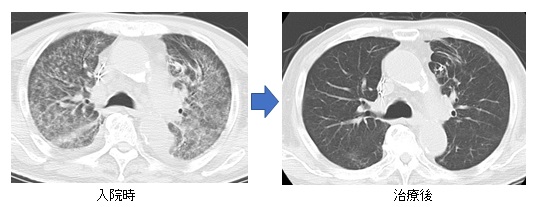

免疫力のない方で問題となる真菌(アスペルギルス感染症)(図7, 8)やニューモシスチス肺炎(図9)に対しては、当科研究室独自に抗体検査や核酸増幅検査を行い、迅速な診断・治療に努めております。国内の研究・検査機関とも協力し、稀な真菌・抗酸菌感染症についても、病原体の同定・診断を試みております(図10) 。

図9. ニューモシスチス肺炎による呼吸不全のため集中治療室にて治療を行いました。入院時には両方の肺全体に広がる白い陰影を認めましたが(左図)、治療により正常に近い状態まで改善しました(右図)。